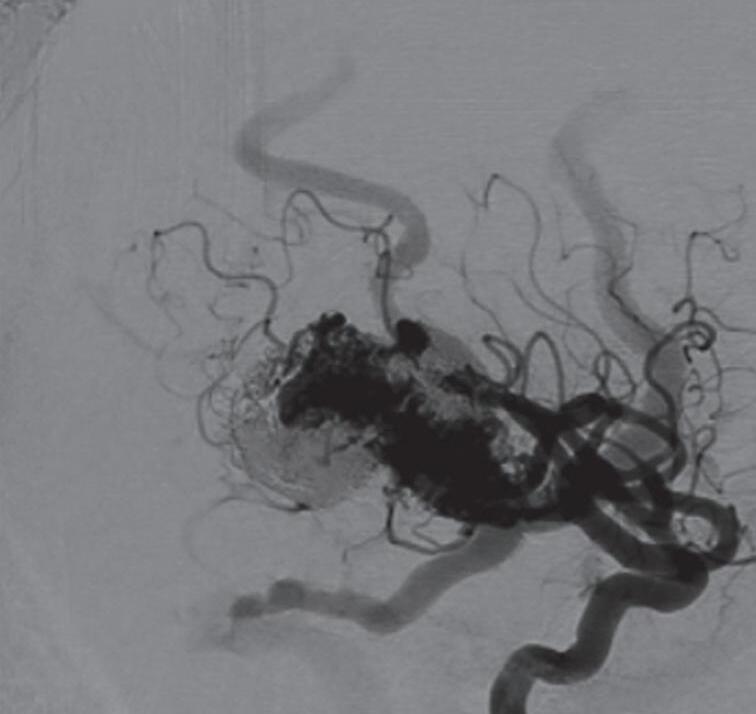

A arteriografia cerebral digital com subtração é considerada o exame padrão-ouro para avaliação das MAV, possui excelente resolução espacial e temporal, o que é necessário para avaliar o tamanho do nidus, a presença de estenose de artéria nutridora, da veia de drenagem, avaliar a presença de aneurismas arteriais e venosos e o fluxo da malformação. Rotineiramente ela deve ser realizada pelo cateterismo dos seis vasos (carótidas internas, externas e artérias vertebrais) e a descrição do exame necessita conter a localização anatômica da malformação, além dos seguintes achados (Figs. 1-24 e 1-25):

Fig. 1-24. Angiograma anteroposterior mostrando MAV nutrida pelas artérias cerebrais média (ramos precoces) setas azuis, com uma grande veia de drenagem – veia cerebral média profunda, seta vermelha relacionada com a ponta do lobo temporal esquerdo. (a-d) Pré-operatório. (e-h) Pós-operatório, mostrando a ressecção completa da lesão e restabelecimento do fluxo regional.